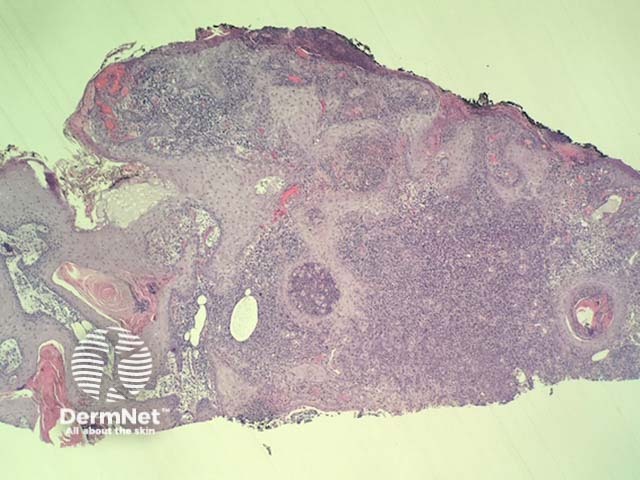

In pseudocarcinomatous hyperplasia in anaplastic large cell lymphoma, histopathology usually shows a cup-shaped keratinocytic proliferation with minimal cytologic atypia resembling a keratoacanthoma (figure 1). Directly adjacent to this proliferation, there is a dermal tumour composed of highly atypical large hematopoietic cells (figure 2,3).

Figure 1